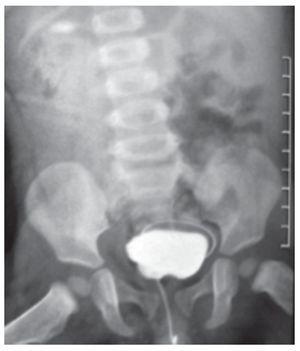

Fue recibido en el Instituto a los cinco meses de edad, durante esta visita se realizó ultrasonido renal y vesical, observando un gran divertículo vesical a la izquierda de la vejiga, cuyo tamaño era de dimensiones similares a la vejiga (Figura 1). La uretrocistografía confirmó el hallazgo del ultrasonido (Figura 2).

Figura 2. Cistouretrograma con evidencia de divertículo vesical de grandes dimensiones en región posterolateral de vejiga A) y B).